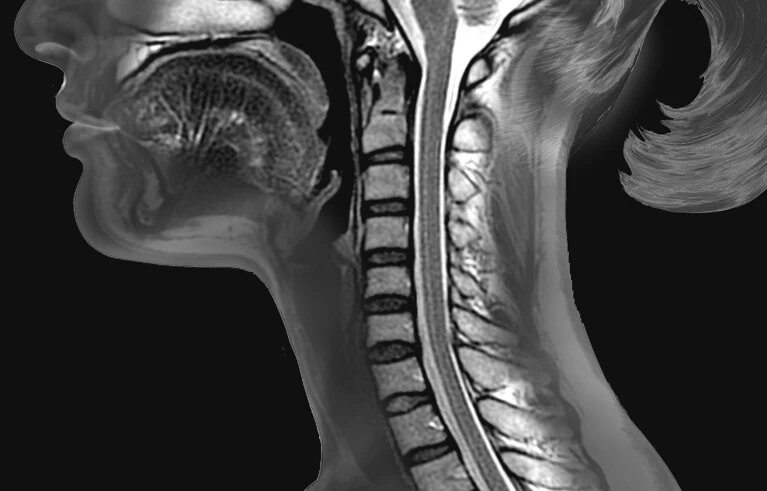

脊髓从大脑底部通过脊椎中心的一根管延伸到下背部。

图片来源:Zephyr/Science Photo Library